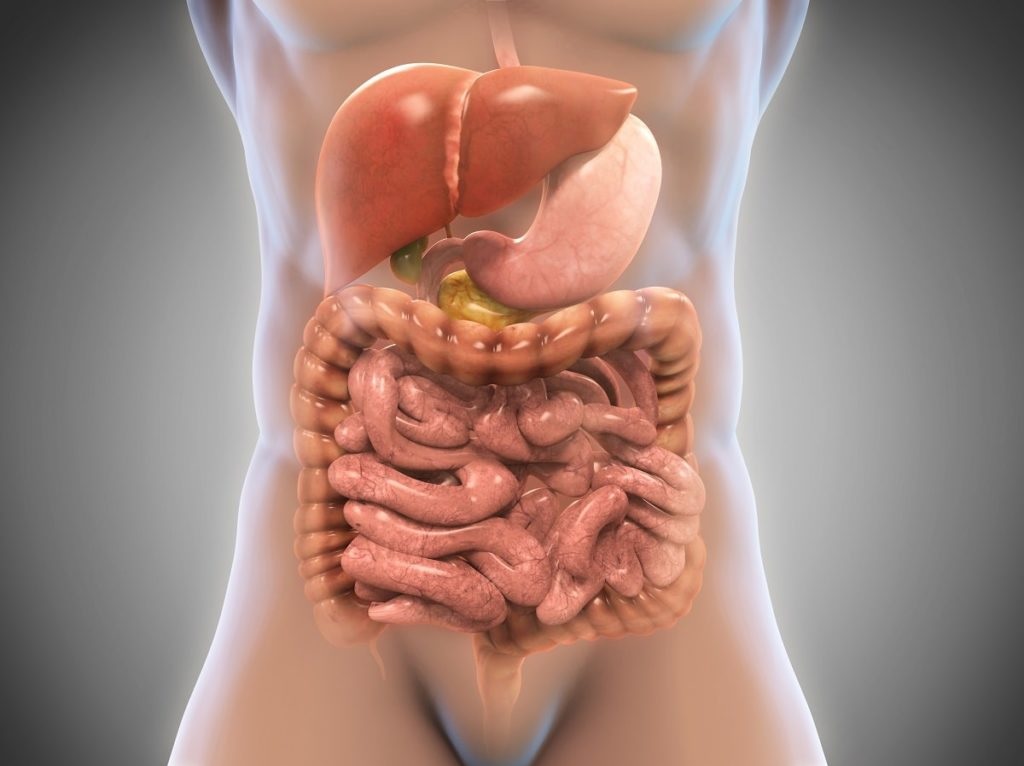

Sistema digestivo

Elsistema digestivo descompone los alimentos en nutrientes que el cuerpo puede absorber y utiliza para obtener energía, crecimiento y reparación de tejidos.

Componentes

- Tracto gastrointestinal: Incluye boca, esófago, estómago, intestinos delgado y grueso, recto y ano.

- Órganos accesorios: Hígado, vesícula biliar y páncreas, que producen enzimas y bilis para la digestión.